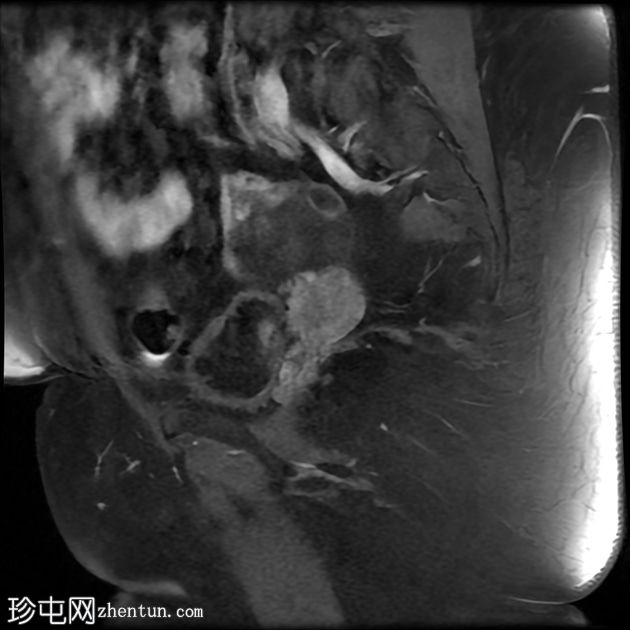

矢状位

T2加权像

1.jpg

左侧卵巢增大,呈弥漫性低T1信号和高T2信号,可见周边卵泡,部分卵泡除周边卵泡周围有环状强化外,无明显实质强化。左侧附件蒂呈漩涡状,提示卵巢扭转。